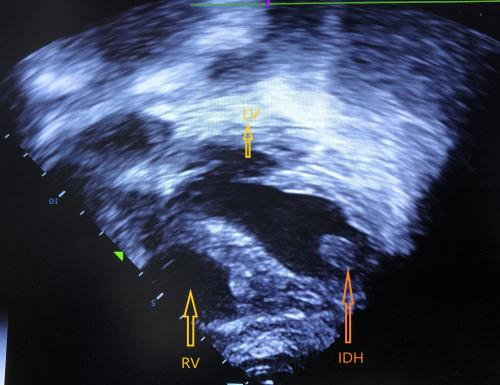

初步诊断患者为休克、心包积液、肺部感染、代谢性酸中毒。为解除心包压塞,于6月27日在血管造影下行心包穿刺引流术,引流量为220 mL,接引流袋(后持续引流出50 mL积血),术后超声心动图提示心功能正常。第2日患者胸闷症状好转,仍有心前区疼痛,给予地佐辛镇痛; 接下来的三日内患者心前区疼痛较前好转,超声心动图提示无明显心包积液,但出现持续性的发热,持续给予碳青霉烯类抗生素抗感染治疗。第6日复查超声心动图提示左室室间隔近心尖处有一液性暗区,并随心动周期晃动(图 1),大小约为1.5 cm×1.0 cm,左心室射血分数为70%,患者神志清楚,无胸闷呼吸困难,偶有心前区疼痛,无血流动力学异常,故未予以任何特殊治疗。第8日超声心动图示液性暗区仍然存在但范围缩小,大小约为1.1 cm×0.7 cm,患者胸痛症状较前缓解,血流动力学仍无异常,故仍未给予治疗,并转至急诊内科普通病房继续治疗。第11日超声心动图提示液性暗区消失(图 2)。第16日患者神志清楚,无胸闷胸痛,心肺听诊无明显异常,遂出院。至2021年12月,经过5个月的随访患者无心功能不全的表现,预后良好。

| IDH为心肌内解剖血肿,LV为左心室,RV为右心室 图 1 患者第6日超声心动图 |

经详细询问病史,结合超声心动图结果,本例患者“心包积液”诊断明确,给予心包穿刺引流解除心脏压塞等对症支持治疗,经积极治疗后患者病情好转,而后于复查的超声心动图中发现一处随心动周期晃动的液性暗区,且在未予以任何干预的情况下自行消失,笔者考虑可能是由于心脏因针刺外伤导致的心肌内解剖血肿(intramuscular anatomy of haematoma, IDH)。